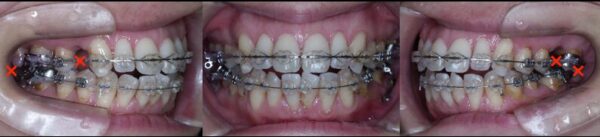

矯正治療開始後12か月の状態です。

矯正終了時の状態です。ここから、メンテナンスに移行しました。